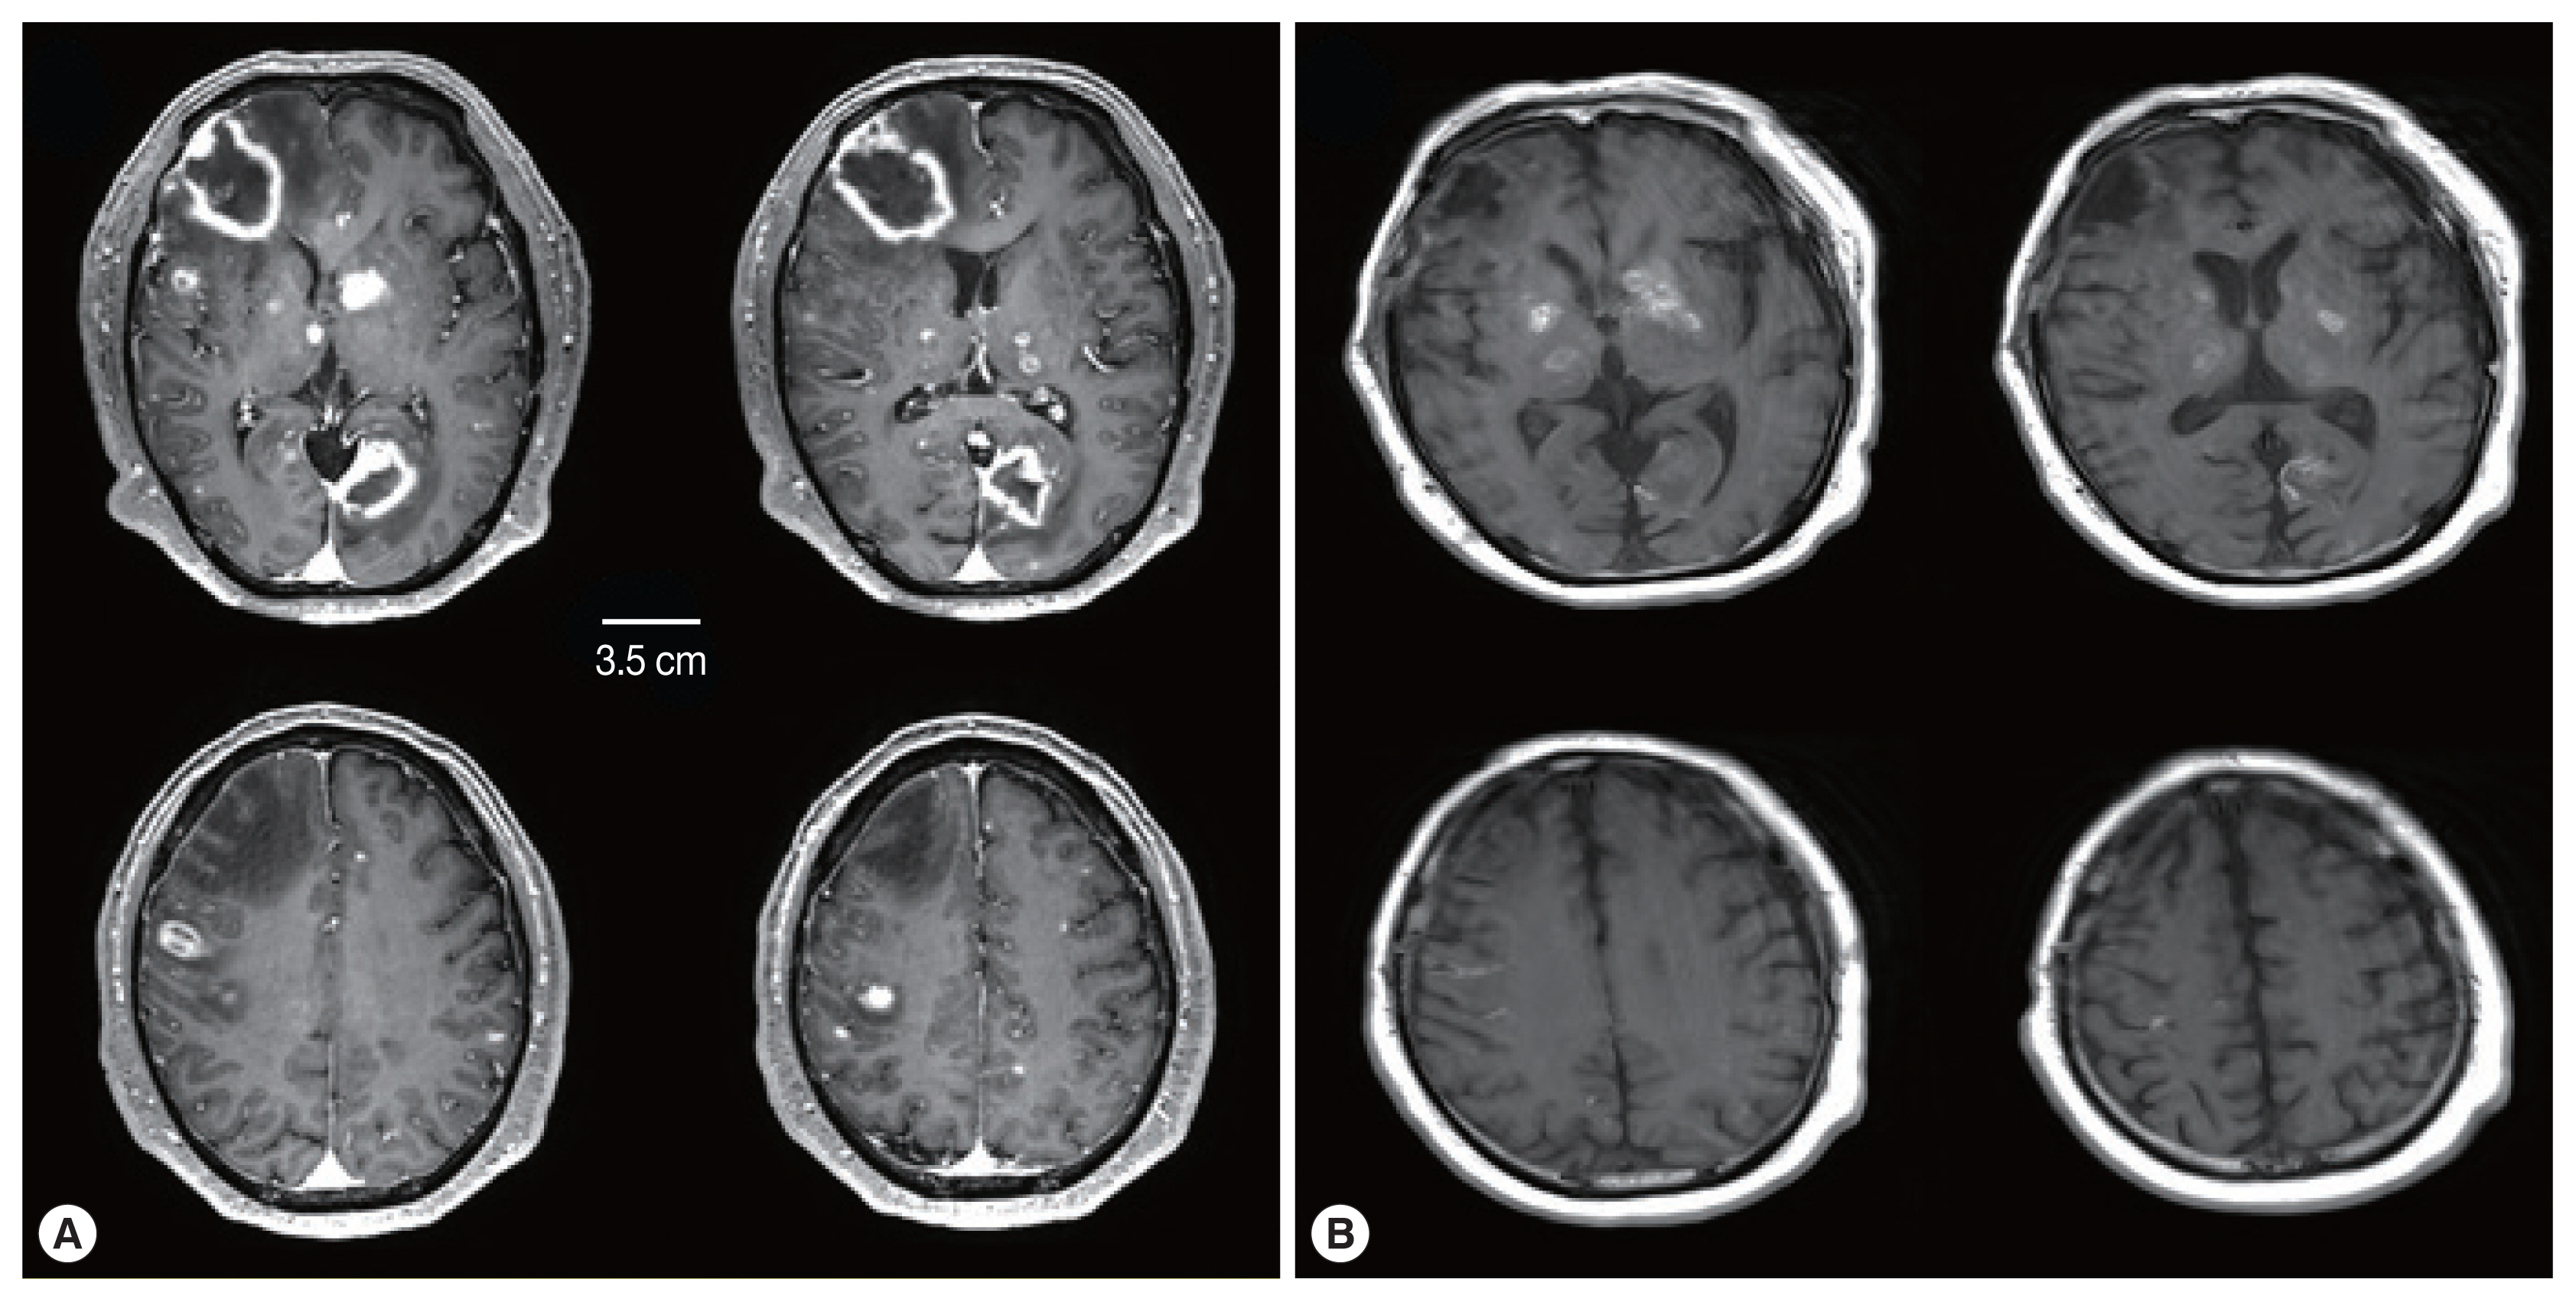

Delayed Cerebral Toxoplasmosis in a Kidney Transplant Patient: a Case Report

The Korean Journal of Parasitology 2022;60(1):35-38.